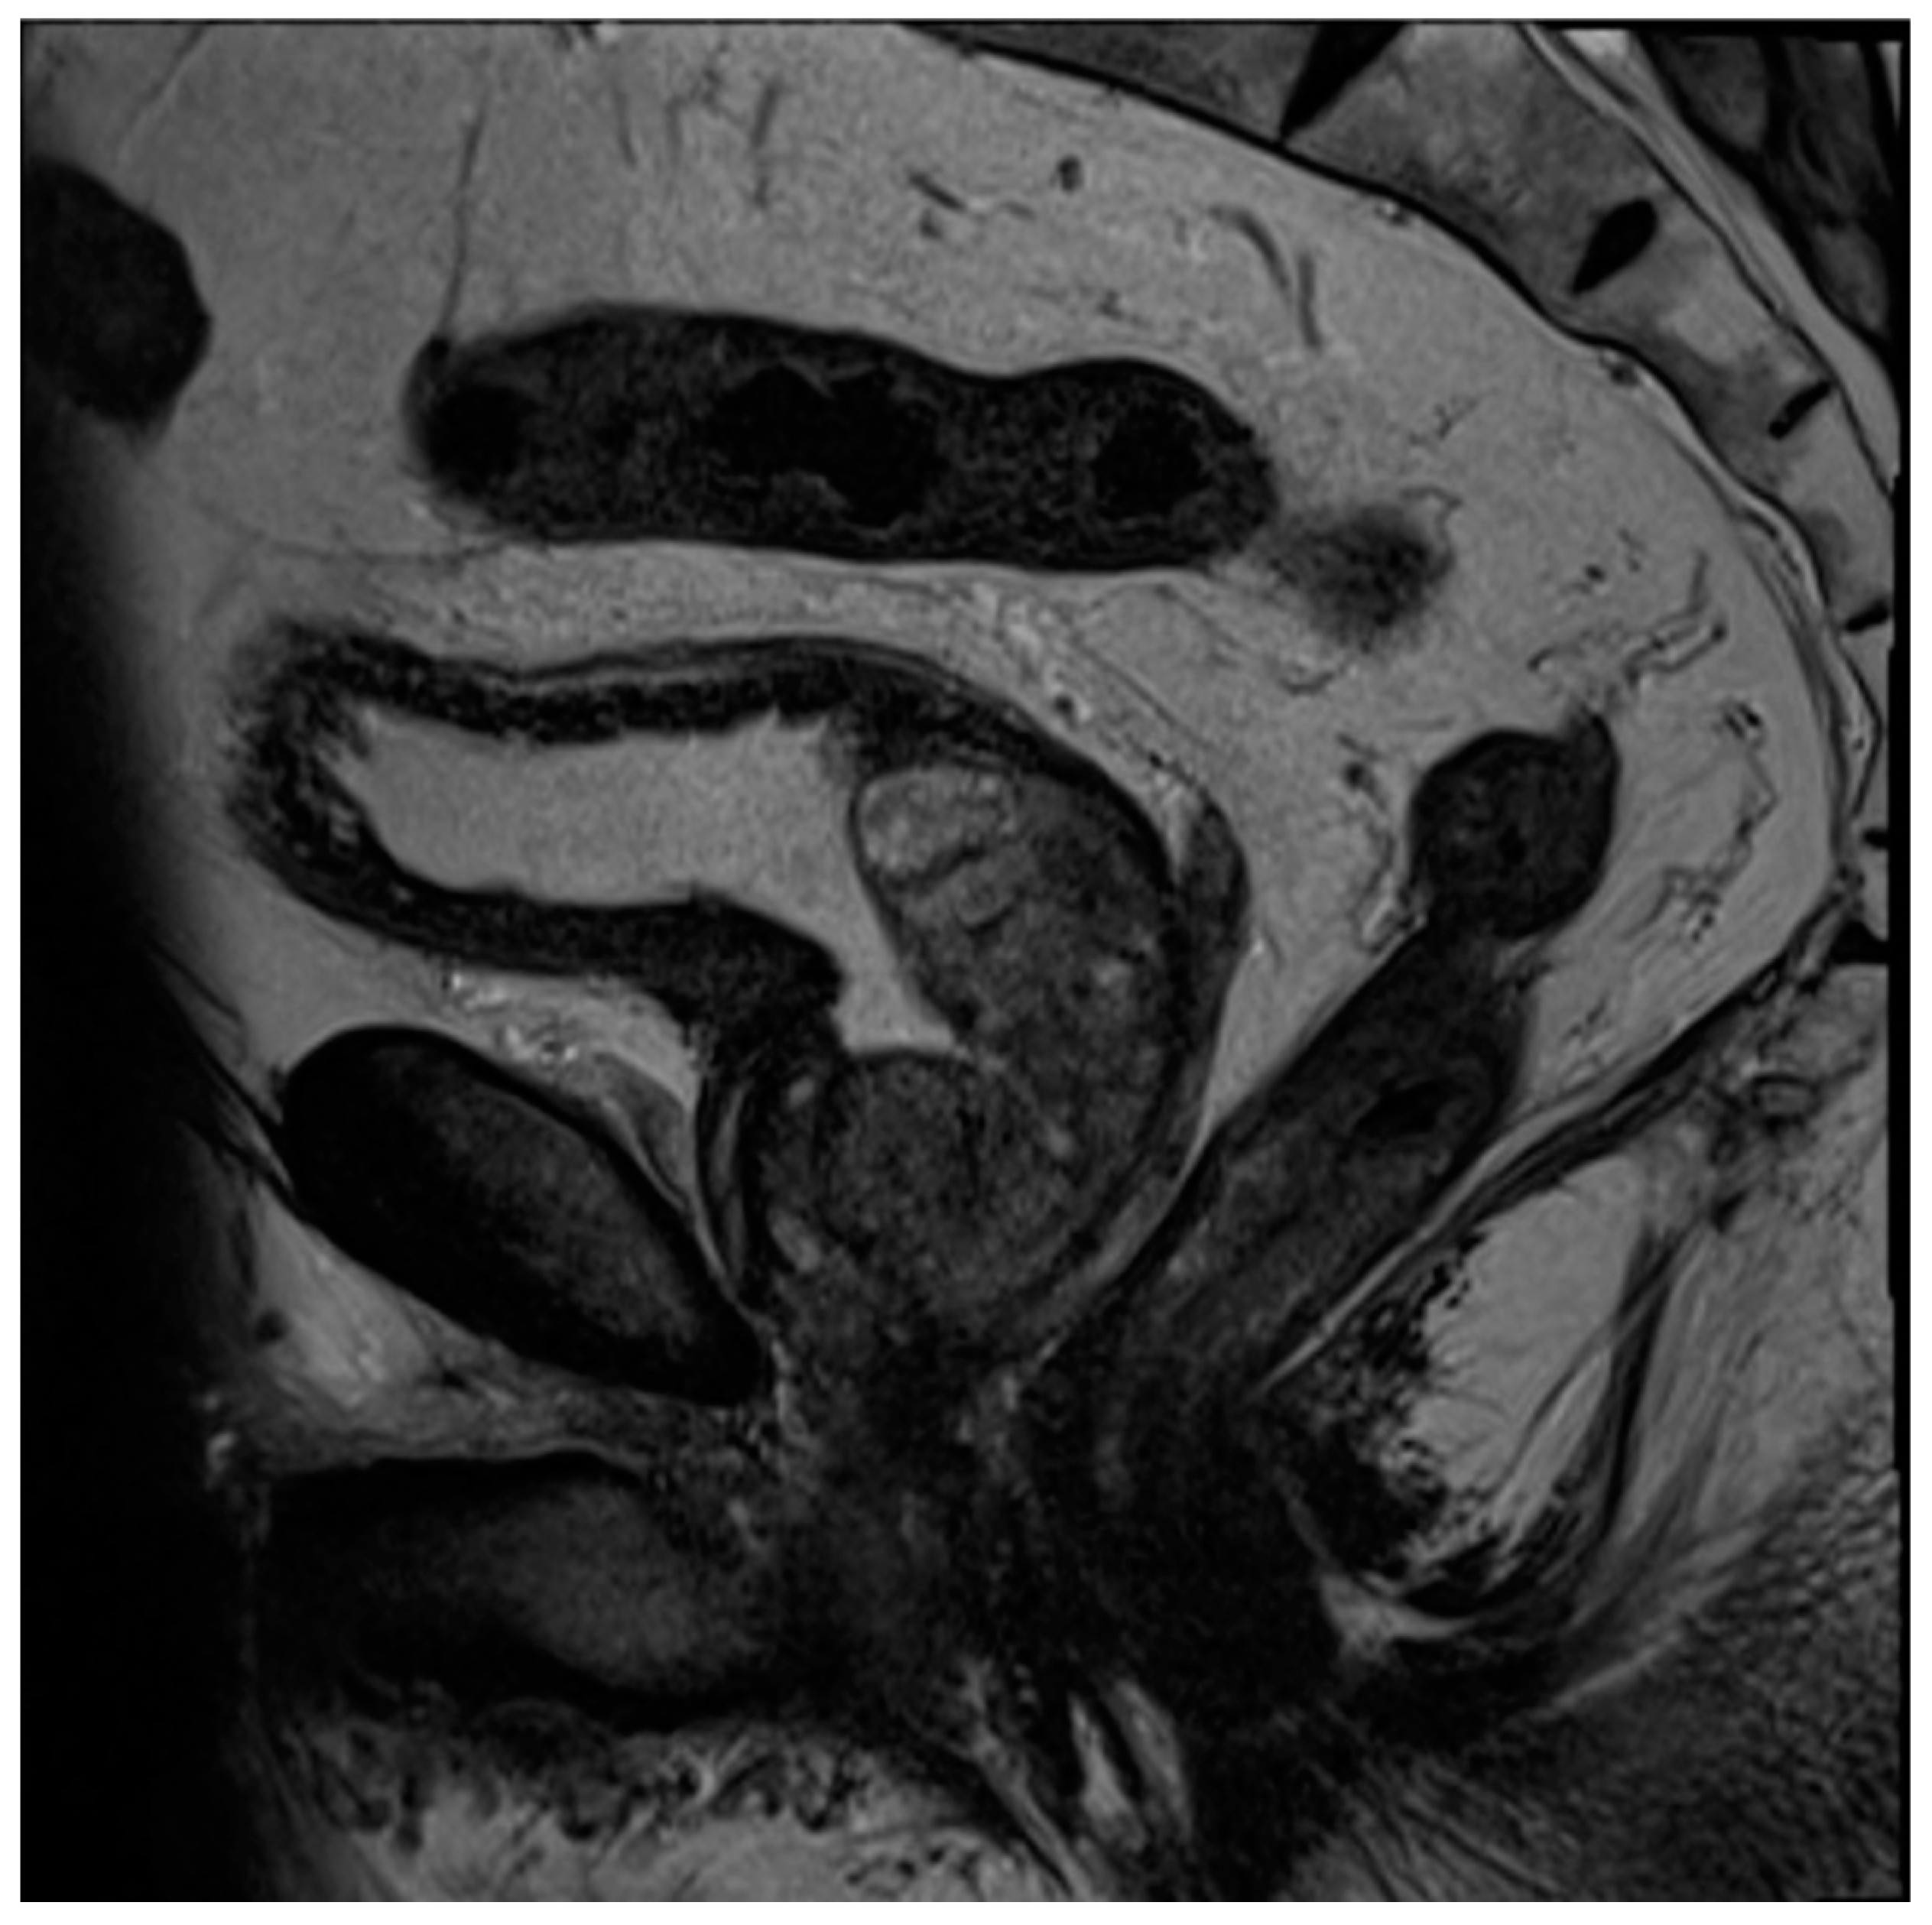

Figure 8. Sagittal T2 image of the pelvis demonstrating a complete absence of the prostate gland with vesicourethral anastomosis following RP.

Radical prostatectomy (RP) is a definitive treatment option for men with prostate cancer in which the prostate and seminal vesicles are surgically removed. The surgical removal of the pelvic lymph nodes may also be offered to men when the chance of nodal metastasis is 2% or higher [81]. Multiple surgical techniques have been described for RP, but the most common approach is robotic-assisted laparoscopic radical prostatectomy (RALP), with up to 90% of all prostatectomies being performed in this manner [82]. Regarding MRI, post-RP changes demonstrate the absence of the prostate gland, with a vesicourethral anastomosis that should have a low T2 signal without early enhancement, nodularity, or restricted diffusion (Figure 8).